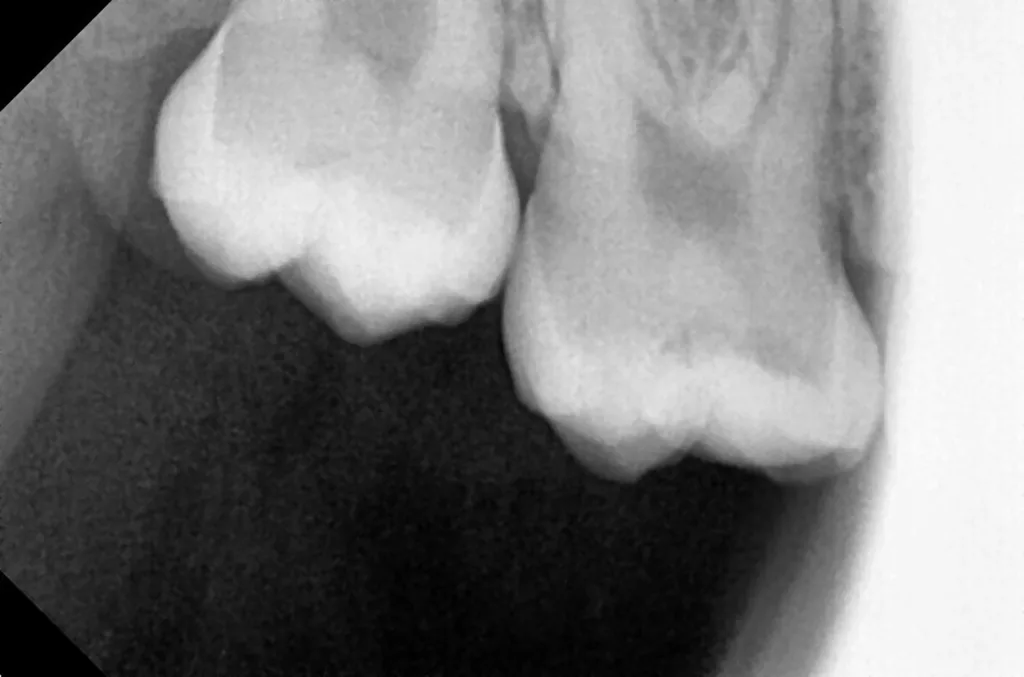

Der elfjährige Junge stellte sich aufgrund starker, anhaltender Schmerzen in regio 47 vor. Der Zahn 47 war gerade im Durchbruch und noch mit einer nichtentzündeten Zahnfleischkapuze partiell überdeckt (Abb. 61). Die Schleimhaut bereitete bei der Palpation keine Schmerzen. Die Perkussion des Zahnes 47 selbst war jedoch positiv. Das Röntgenbild zeigte unter dem komplett erhaltenen Zahnschmelzmantel einen umfangreichen runden Dentindefekt, der fast bis zum Pulpakavum reichte. Der kortikale Knochen der Wachstumszone war praktisch nicht verändert, es war jedoch eine Erweiterung des Parodontalspaltes zu beobachten (Abb. 62). Aufgrund der vorliegenden klinischen und radiologischen Befunde wurde vorläufig eine PEIR des Zahnes 46 (Grad 3 der Läsion nach Seow) diagnostiziert, die durch eine akute Pulpitis verkompliziert wurde. Der Patient und seine Mutter wurden ausführlich über die Behandlungsmöglichkeiten aufgeklärt. Aufgrund der Komplexität des Falles und der Angst des Patienten erfolgte die Behandlung in ITN.